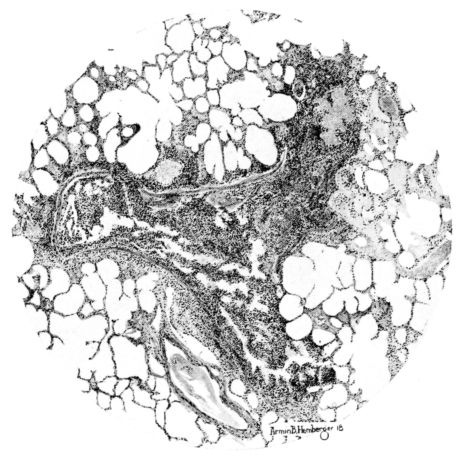

FIG. I. AUTOPSY NO. 99. ACUTE HEMORRHAGIC AND ULCERATIVE LARYNGOTRACHEITIS.

FIG. I. AUTOPSY NO. 99. ACUTE HEMORRHAGIC AND ULCERATIVE LARYNGOTRACHEITIS.

FIG. XIII. AUTOPSY NO. 96. RIGHT LUNG. A WATER COLOR DRAWING OF A GROSS LUNG IN THE ACUTE STAGE. NOTE THE SIZE OF THE LUNG, THE HEMORRHAGES ON THE PLEURAL SURFACE, AND THE BLUE AREAS OF CONSOLIDATION.